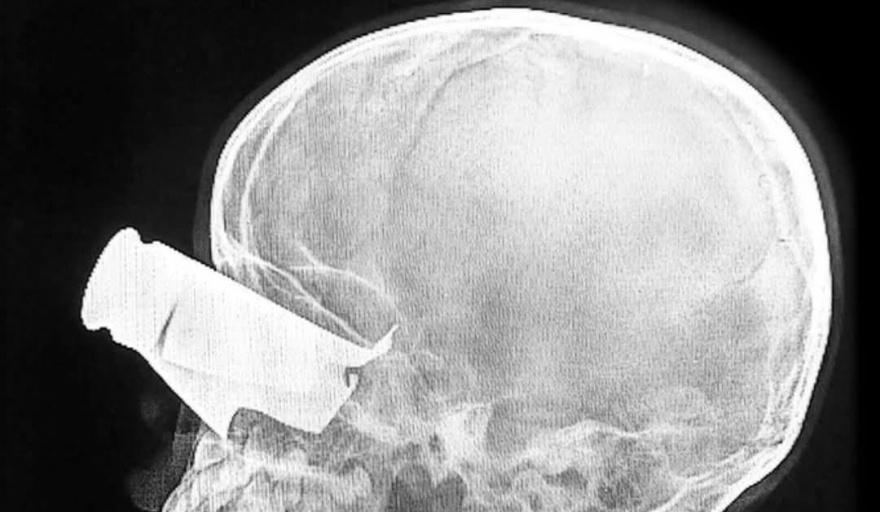

En Sudán, el dato no es menor ni aislado. Médicos Sin Fronteras documentó que sus equipos han tratado 167 heridos graves en un período de dos semanas, con lesiones compatibles con explosiones de municiones lanzadas por drones en áreas civiles. Las descripciones no dejan margen para la ambigüedad: heridas penetrantes en tórax y abdomen, traumatismos craneoencefálicos, múltiples fracturas, amputaciones. Entre los casos, un niño de nueve años con metralla en el ojo, fracturas faciales extensas y dos dedos amputados, trasladado a Yamena para cirugía especializada, con alta probabilidad de discapacidad permanente.

El uso de drones introduce una dimensión específica. Se trata de sistemas que permiten atacar sin exponer tropas propias, reducir costos políticos internos y operar a distancia. En el discurso militar contemporáneo, se presentan como instrumentos de precisión. Sin embargo, cuando el resultado reiterado son heridas en niños, amputaciones y traumatismos craneales en barrios residenciales, la precisión deja de ser un atributo técnico y se convierte en una cuestión jurídica.